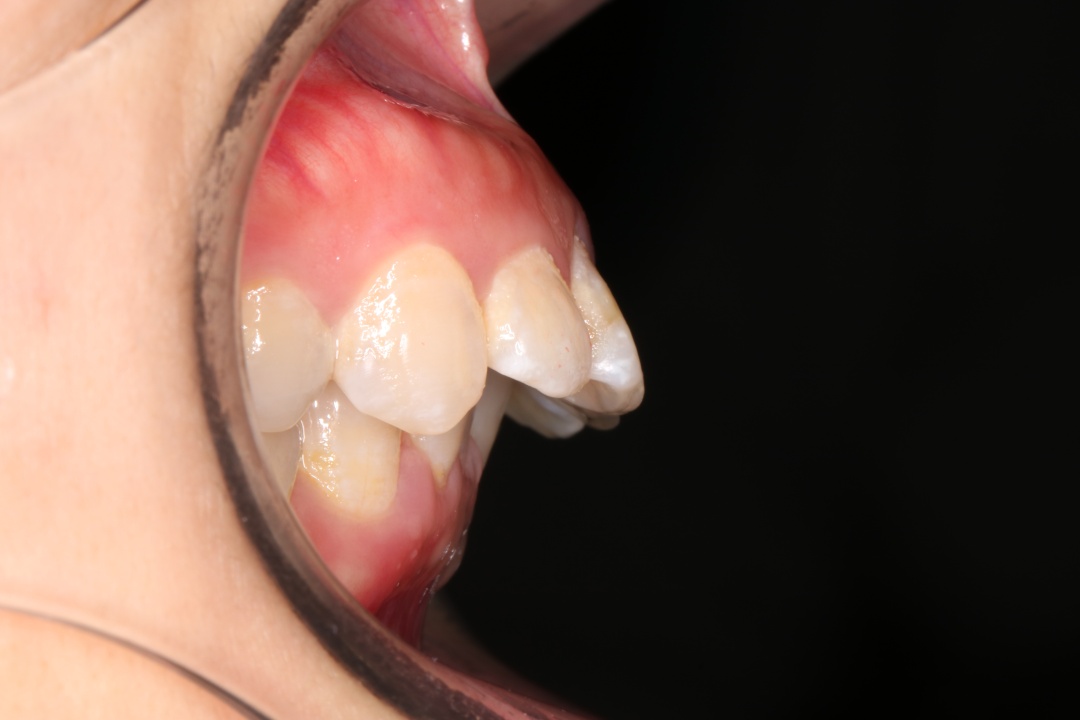

“龅牙”患者常常表现为开唇露齿,自然状态下双唇不能闭拢,微笑时牙龈外露过多,常常伴有颏后缩,强迫闭口时,下唇下方与颏部之间有明显的软组织隆起。口内上下前牙唇倾,常伴拥挤不齐,前牙深覆颌、深覆盖。

因为口呼吸的时候,下巴会后旋,外界的气压会压迫我们的颊肌,然后颊肌会压迫牙弓,让上牙弓变得特别狭窄,并且突出去,上颚特别高拱,龅牙就会越来越明显。